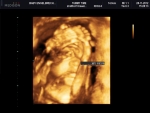

Alma PreNatal2